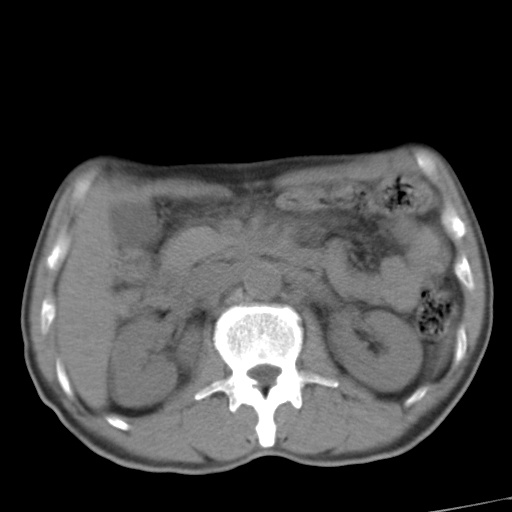

标题: CT17975:请求会诊。男、57岁。上腹部胀痛2天。临床诊断:糜 [打印本页]

标题: CT17975:请求会诊。男、57岁。上腹部胀痛2天。临床诊断:糜

考虑胃癌并肝脏及腹膜后淋巴结转移;不排除淋巴瘤。

肝内转移瘤,腹腔及腹膜后淋巴结转移。